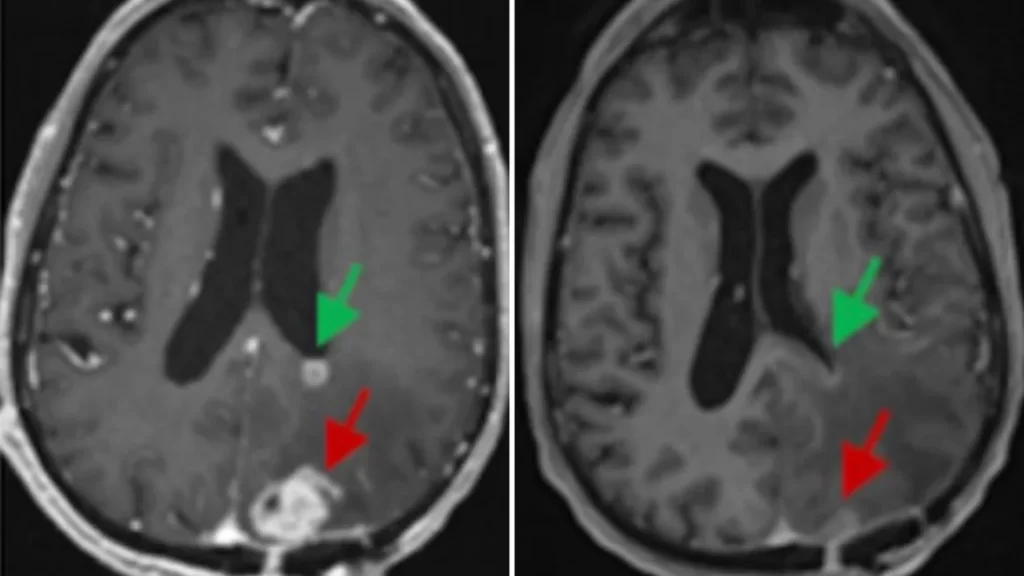

After a single 10-milliliter infusion of about 10 million CAR-T cells, Fraser’s tumor began to shrink. On an MRI scan the next day, it was nearly 20% smaller, and within weeks, it was barely detectable. He’s seen no progression of his cancer for about six months now, according to his doctors. He’s just had his third brain surgery.